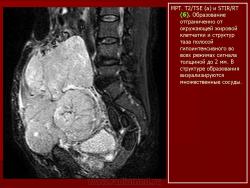

Онкология. Фибросаркома забрюшинного пространства. +

Фибросаркома забрюшинного пространства.